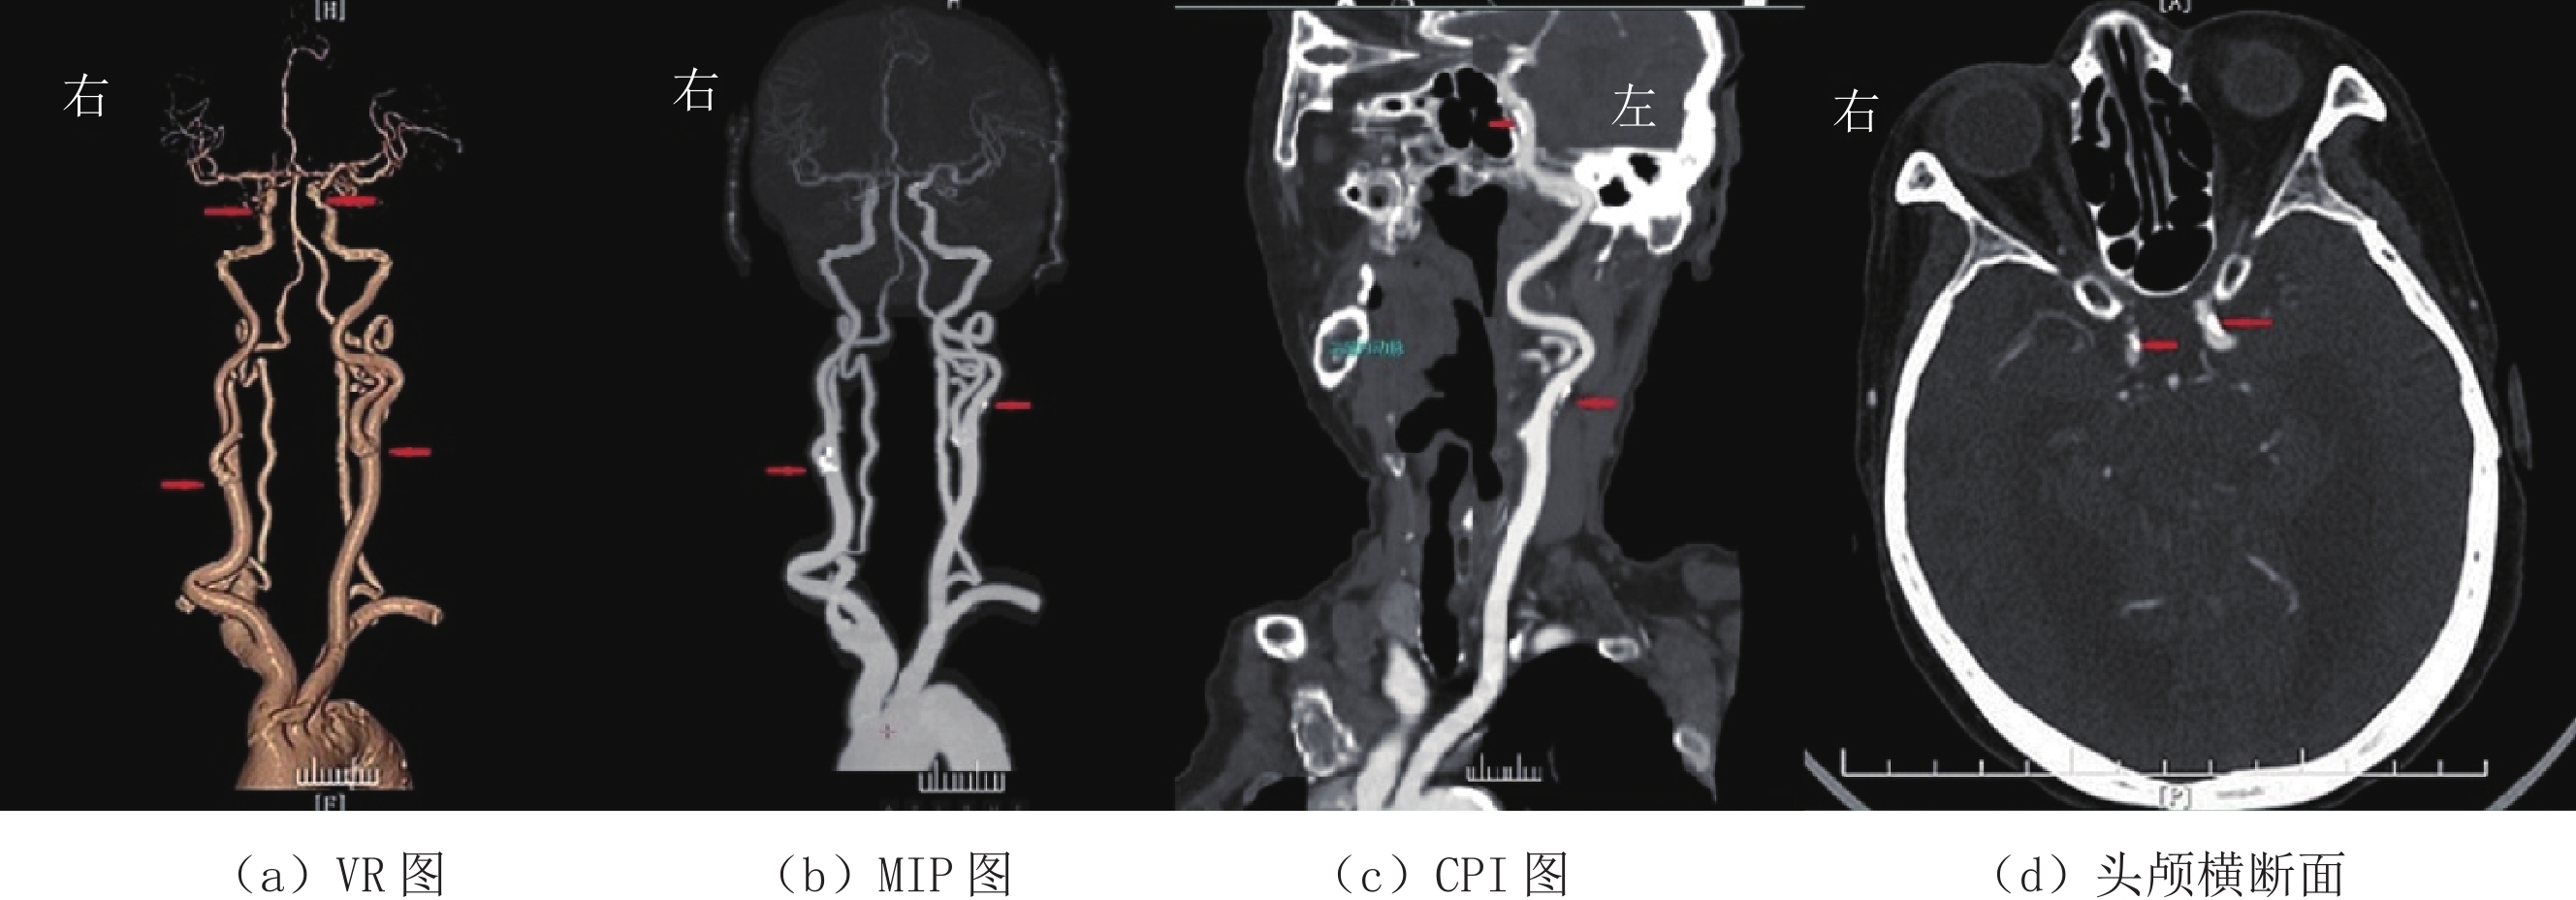

1.4.2 图像主观评分

采用双盲法由两位高年资主治医师对3组患者的横断面图像、VR、MIP以及CPI图像质量进行评分(图1~图3)。评分标准采用5分法[6],5分:图像质量好,血管与组织对比鲜明,细微解剖结构清晰,噪声小;4分:图像质量较好,血管与组织对比较好,解剖结构较清晰,噪声较小;3分:图像质量一般,血管解剖结构显示一般,噪声略大;2分:图像质量较差,血管解剖结构不清,噪声较重;1分:图像质量差,血管解剖结构不清,噪声极为严重。评分大于或等于3分视为满足诊断要求。

(1)众所周知,X线经过人体时会产生康普顿效应和光电效应;X线光子能量会随着管电压的下降而下降,当X线光子能量接近碘原子的K临界值(33 keV)时衰减值最大,这样导致所测得的CT值会随着管电压的下降而增高[13-15]。本研究结果显示:管电压从120 kV降到100 kV、80 kV时,大脑中动脉M1段血管的CT值分别为(334.21±69.42)HU、(385.00±85.53)HU、(502.50±110.17)HU,与学者的研究基本一致[10,16-18]。由于含碘血管腔的CT值是头颈部CTA图像质量的关键所在,也是观察血管病变和VR、MIP及CPI成像的基础。研究发现[16-18]血管腔内的CT值以350~550 HU时最佳,过低或过高都不利于血管细节的显示,会影响粥样斑块的显示和血管狭窄程度的判断。本研究大脑中动脉M1段血管CT值在管电压等于100 kV时最接近这个数值。同时,从本研究3组图像质量主观评分也可以看出管电压为100 kV时评分最高。两组数据都可以证明,管电压在100 kV时,图像质量最好。

(2)图像噪声是评价图像质量另外一个很关键的因素[10,19]。管电压一旦下降,X线的质量和穿透力都会随之下降。特别是颅内段血管,由于高致密颅骨的遮挡,X线光子到达探测器的数量便会减少,SD值增大,图像颗粒感明显增大,影响对病变细节的观察。本研究显示,管电压降至80 kV时,主动脉弓和大脑中动脉M1段的SD值明显上升,上升幅度为60% 和86%,并不利于病变细节的观察。